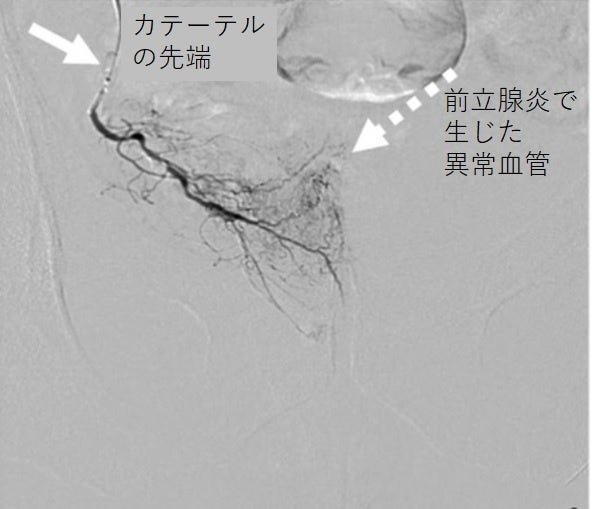

これらの炎症は不要にできた血管「モヤモヤ血管」と一緒にできる神経から痛みを誘発していることが最近の研究でわかってきました。そこで当クリニックでは慢性的な痛みの原因が前立腺にできるモヤモヤ血管にあると考え、造影MRIを用いて患部を確認したところ、9割近くの患者さんに痛みの炎症であるモヤモヤ血管が見つかりました。

この慢性前立腺炎の治療に対して、当クリニックは新しい「カテーテル治療」を開発しました。この治療法は2024年4月25日に横浜みなとみらいで開催された第111回泌尿器科学会で成果を発表しています。

「カテーテル治療」は30分~1時間で終わる日帰り治療です。メスを使わず、鼠蹊部から極細のカテーテルを通して患部に薬剤を注入します。傷跡はバンドエイドで止血し治療は終わりです。日常生活にも影響なく体に負担をかけない治療です。重篤な副作用は報告されていませんが注射した部位に内出血を起こしたり、蕁麻疹がみられることがまれにあります。